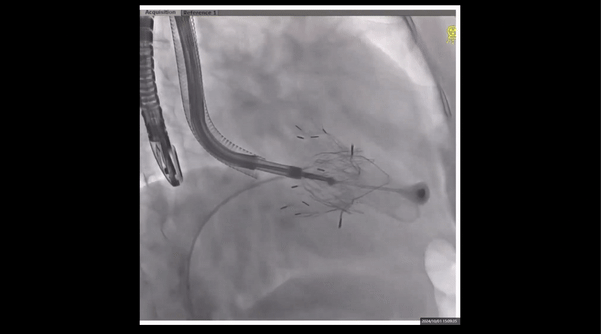

術(shù)前右室造影

夾持件位置確認(rèn)

室間隔位置確認(rèn)

術(shù)后即刻返流

瓣膜釋放